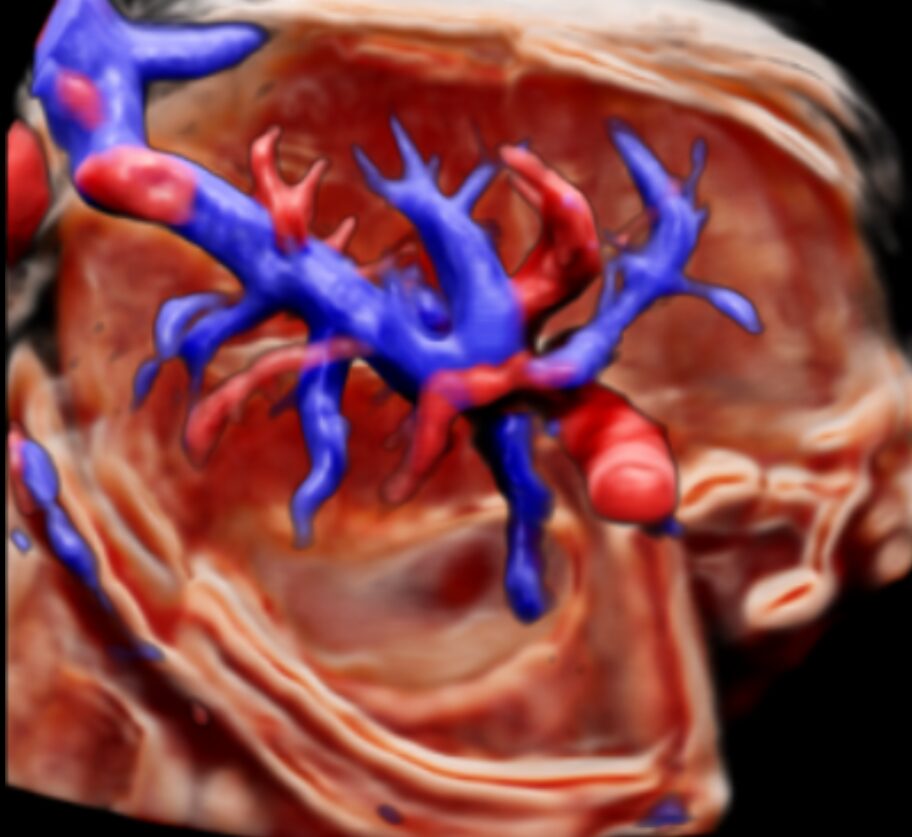

- MV-Flow™ / MV-Flow 3D — визуализация микроциркуляции и медленного кровотока.

4. MV-Flow™ и LumiFlow™

MV-Flow показывает микроциркуляцию и медленный кровоток с высокой детализацией. LumiFlow добавляет объёмное отображение и направление потока, помогая лучше понимать сосудистую структуру тканей.